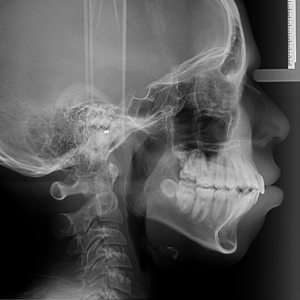

La radiografía lateral de cráneo es una técnica de imagenología utilizada para obtener una vista detallada del cráneo desde un ángulo lateral. Esta radiografía es especialmente valiosa en diversas áreas de la medicina y la odontología, proporcionando información clave sobre la estructura ósea y las relaciones anatómicas del cráneo. Características de la Radiografía Lateral de...